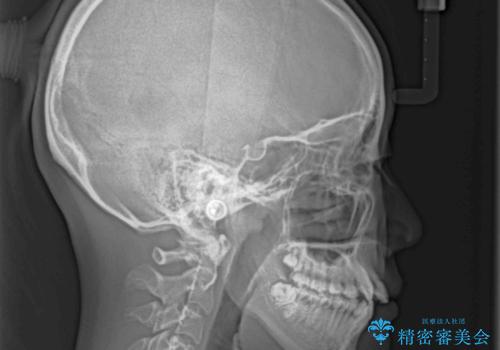

上顎骨幅が狭い 急速拡大装置を併用した抜歯矯正

検査を行った結果、上顎骨の横幅が相対的に狭いことが分かり、叢生が強いことから、急速拡大装置にて上顎骨を側方に拡大することで、叢生の解消と奥歯の咬み合わせ改善を図ることとしました。

一般的には上下左右の第一小臼歯4本を抜歯する必要がありますが、拡大量によっては非抜歯矯正の適用となる可能性があるため、まずは非抜歯矯正で治療を開始し、抜歯が必要と判断された時点で速やかに4本抜歯を行うこととしました。

急速拡大後、歯列はきれいに並んだのですが、口元が出っ歯になってしまったため、速やかに抜歯を行い、治療期間がいたずらに遅延することのないようにしました。